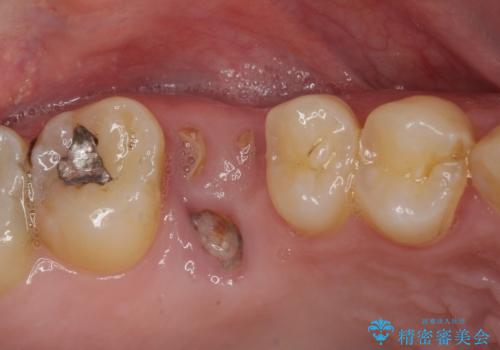

- 奥歯に問題が多くて困っているとのことで来院された患者様です。

また、欠損や根管治療の必要な歯など、むし歯による問題も多く散見されました。